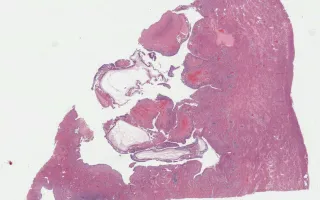

Invasive hydatidiform mole is uncommon, and is defined by the occurrence of a molar pregnancy (complete or partial) that invades the uterine smooth muscle and/or the vasculature. In this case, the features are of a complete hydatidiform mole (large cavitated villi, abundant trophoblast hyperplasia with both cytotrophoblast and synctitiotrophoblast cells) in which villi can be seen in the myometrium and impinging on myometrial vessels. The molar villi demonstrated loss of p57 staining in cytotrophoblast and stroma (slide not shown.)

Chang, M. Uterus, Invasive complete hydatidiform mole. Digital Laboratory Medicine Library, Dept of Laboratory Medicine & Pathobiology, University of Toronto. Published